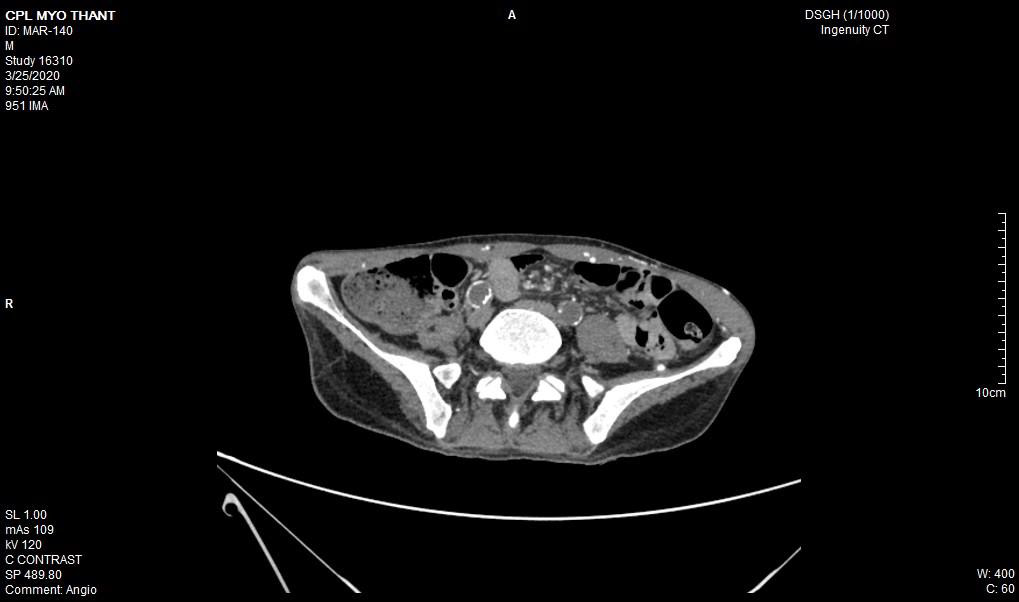

As his left femoral artery pulsation became weak and thus, CT Aortogram was done (4 weeks after symptom onset of right femoral artery occlusion). It revealed extensive thrombosis with complete obstruction of abdominal aorta starting below the level of celiac trunk- both renal arteries and both iliac arteries. The calcifications of the arterial wall at aortic arch, thoracic and abdominal aorta and both iliac vessels were seen too. (Figures 5-11) Thus, he had severe atherosclerosis due to hypertension and heavy smoking. Occlusion of both renal arteries explained his high blood pressure. The cholesterol and uric acid level were normal. He was treated with atorvastatin, aspirin, clopidogrel, antihypertensives, wound care, physiotherapy, intensive nursing care nutritional support and antibiotics.

This patient had on going ischaemia as the wound was not healing well and diminished left femoral pulsation. And it was a clinical clue to arterial obstruction at higher level – above femoral artery. It was proved by CT angiogram.